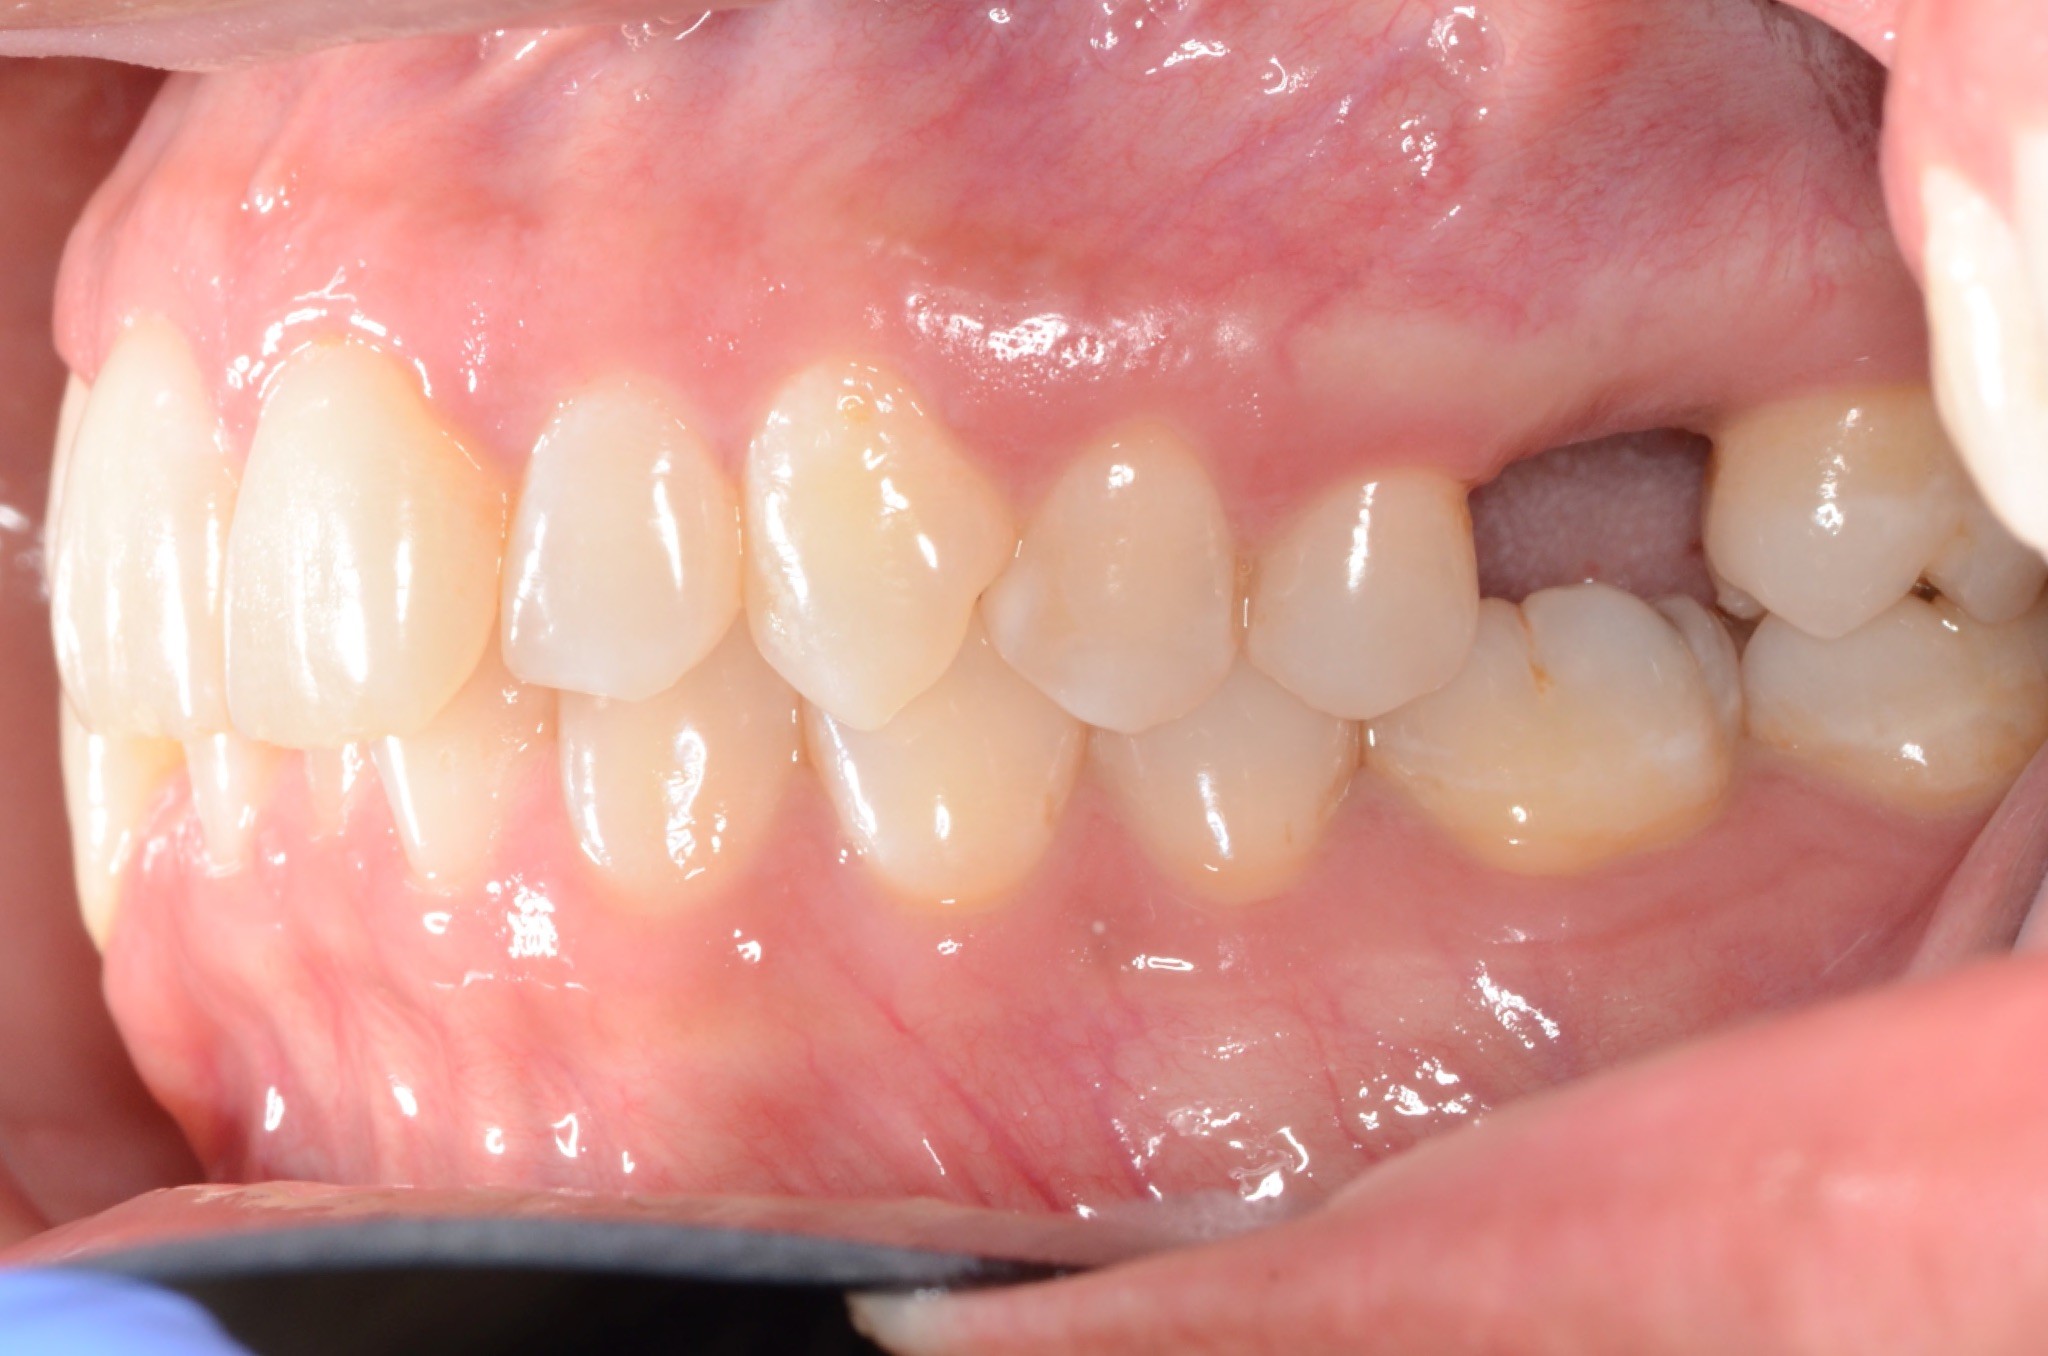

Diagnosis: Lower anterior crowding, LL3 crossbite, deep bite, missing UL6.

Adjuncts: Bite ramps, attachments, IPR

INTRAORAL